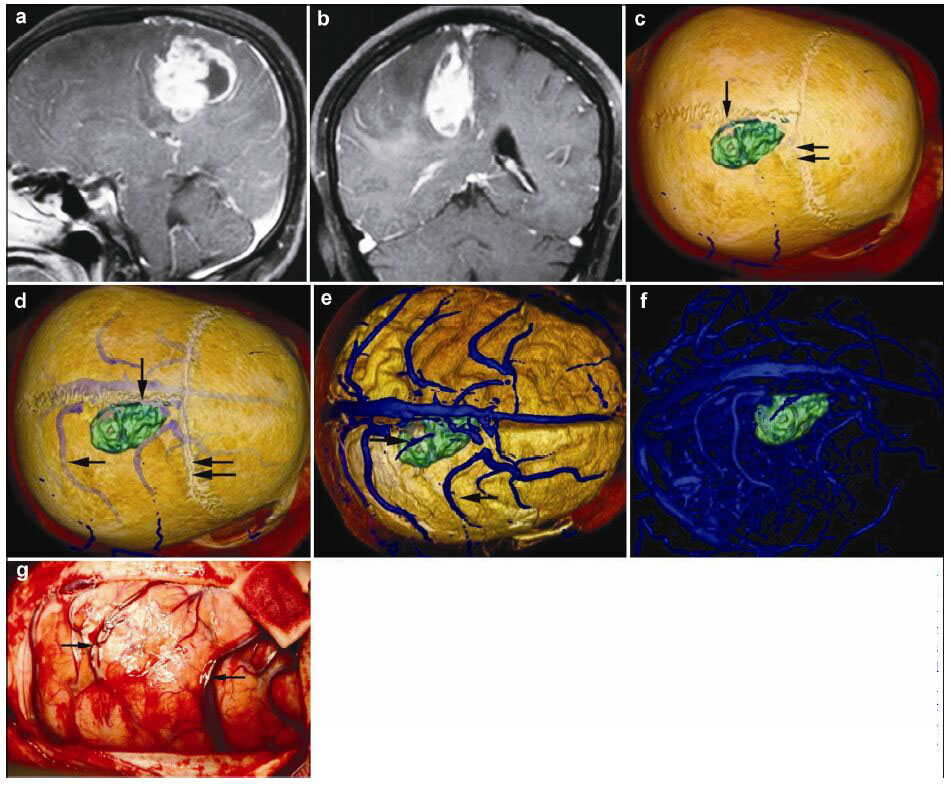

| Figure 3 Magnetic resonance imaging, reconstruction images, and actual operative view in a 62-year-old female patient with a malignant meningioma in right frontal lobe. (a, b) T1 enhancement scans: The tumor presented as heterogeneous enhancement. (c) 3D reconstruc-tion: The tumor located behind the coronary suture (horizontal double arrow) and adjacent to sagittal suture (vertical single arrow). (d)3D reconstruction (skull semitransparent): This picture not only shows the relationship between tumor and sutures (coronary suture, horizontal double arrow; sagittal suture, vertical single arrow) but also shows the relationship between tumor and the superior cerebral veins (horizontal double arrow). (e) 3D reconstruction (do not show the skull): The tumor locates between two superior cerebral veins (horizontal single arrow). (f) 3D reconstruction: This picture only shows the tumor and veins. (g) Intraoperative situation: The intraoperative situation is consistent with 3D reconstruction images. |